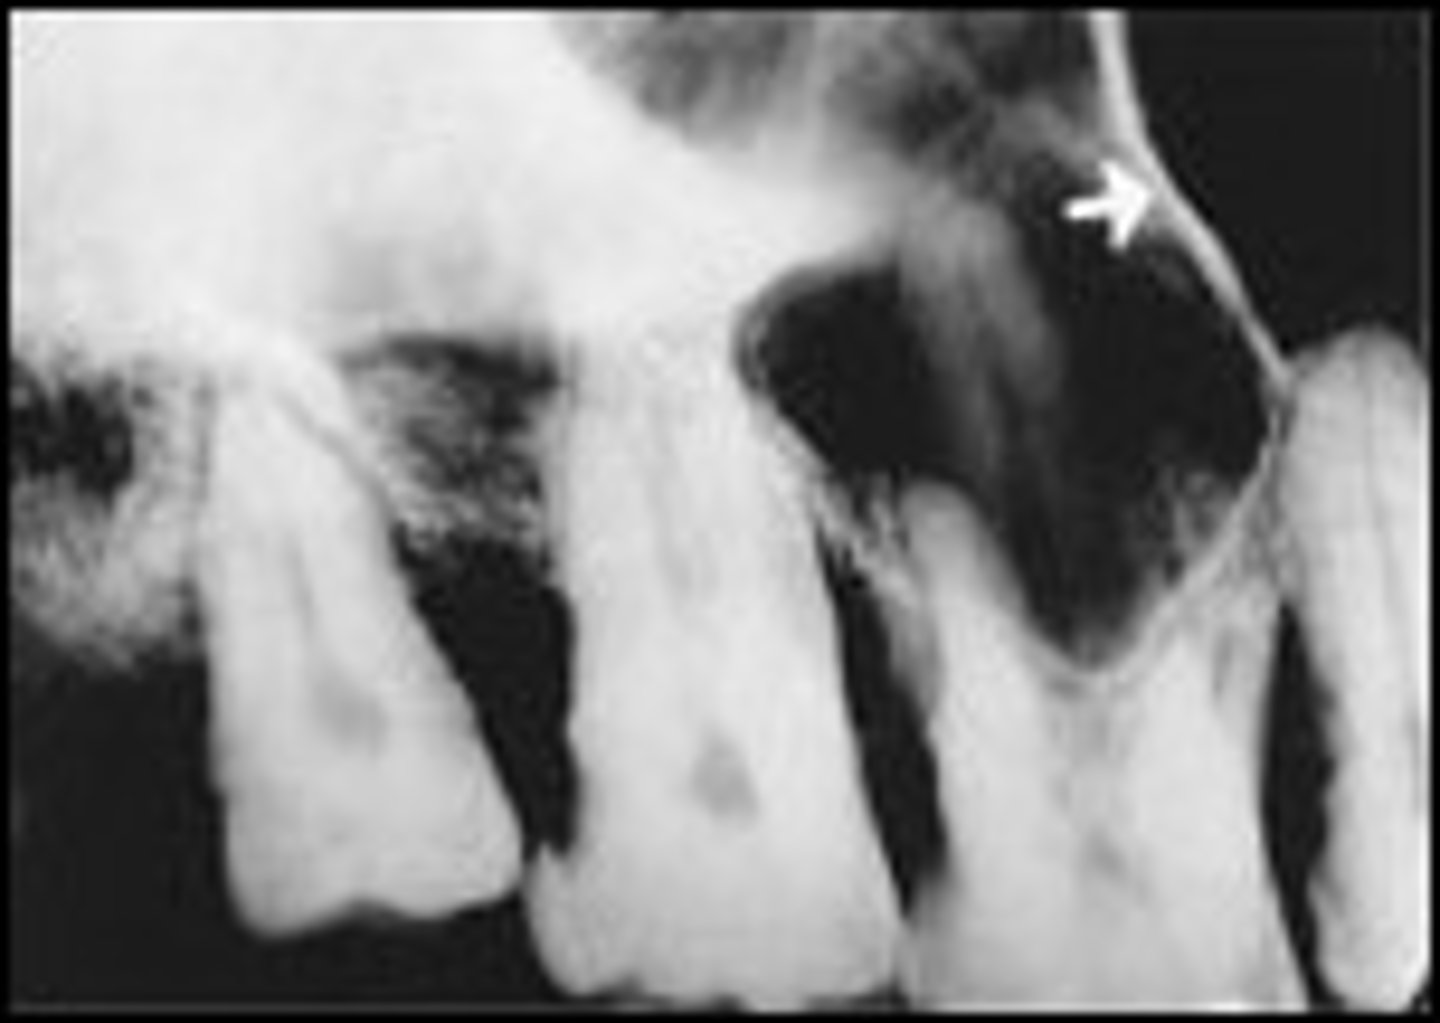

Nutrient canals

What is the radiolucent structure seen here?